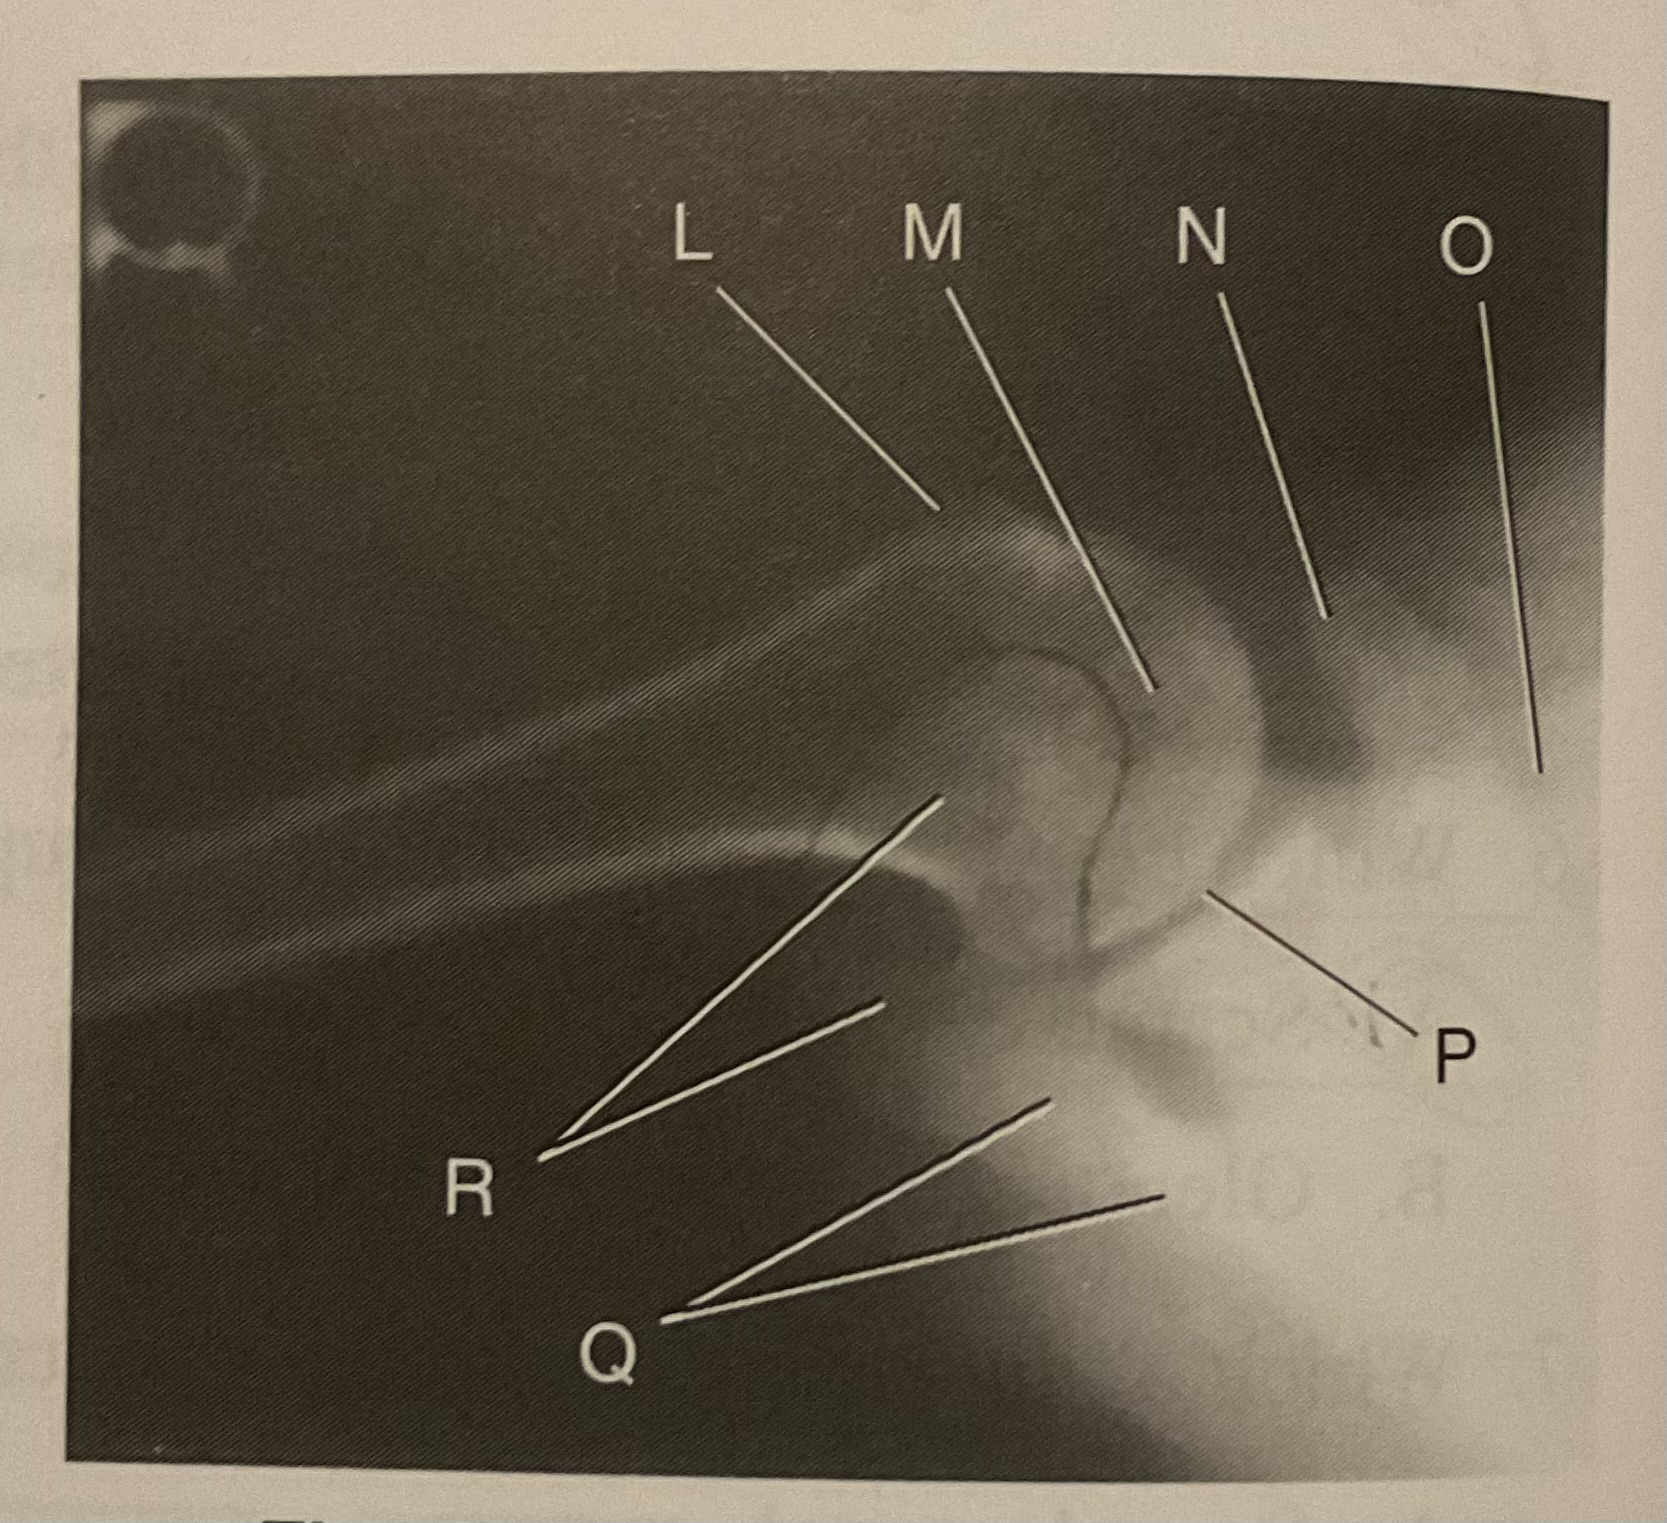

What AP projection does this image represent?

External

L?

Lesser tubercle

M?

Head of humerus

N?

Coracoid process

O?

Clavicle or lateral extremity of clavicle

P?

Glenoid cavity or Scapulohumeral joint

Q?

Spine of scapula

R?

Acromion of scapula

What is the correct term and method for the projection seen in this image?

Inferosuperior axial projection